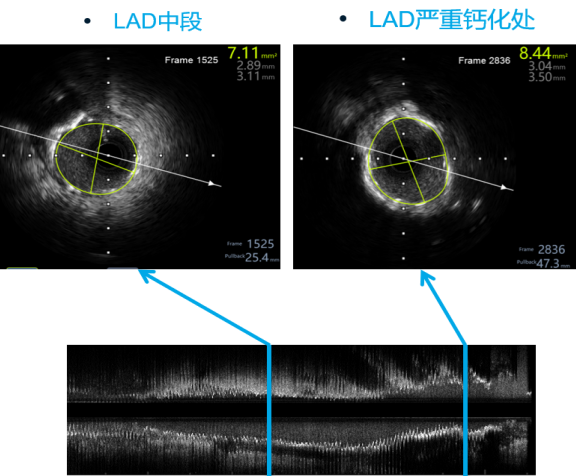

沿LAD导丝送IVUS导管至LAD狭窄病变远段,检查示LAD-LM最小管腔直径1.58mm、最大管腔直径2.02mm、最小管腔面积2.4mm²,局部呈现270-360度钙化。

Shockwave 3.5*12mm于LAD-LM病变4atm-6atm反复震波扩张8次 每次10s

随后沿LAD导丝送入Shockwave 3.5*12mm球囊于LAD-LM病变处,由远及近,以4atm扩张触发血管内冲击波,每组10个,后将Shockwave导管扩张至6atm维持10-15s以检验扩张效果、最大化管腔获益,后回抱导管,进行下一组冲击波治疗,共循环发放8组脉冲,复查IVUS提示局部环形钙化环断裂。

严重钙化处管腔扩大